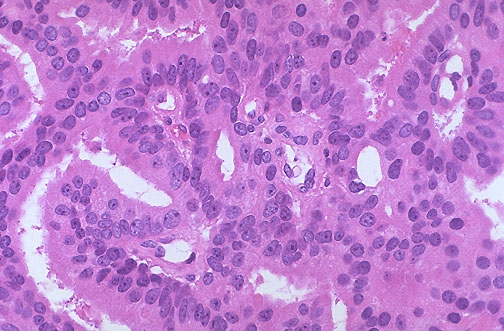

A hallmark of prostatic adenocarcinoma is the presence of prominent large nucleoli, as seen here.